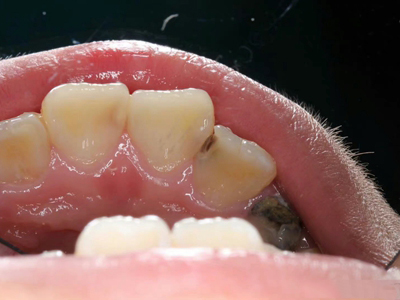

年轻恒牙龋指的是儿童萌出不久的第一恒磨牙龋病和上颌恒切牙龋病,其中第一恒磨牙龋病占年轻恒牙龋的90%,发病早,进展快,可表现为白垩色斑片、点隙窝沟墨浸状龋坏或龋洞。本病的发生和年轻恒牙的特点以及儿童饮食、口腔卫生等因素有关。

年轻恒牙龋好发于第一、二恒磨牙(牙合)面、邻面,上颌中切牙邻面,多为急性龋,龋坏进展快。平滑面的早期龋多为白垩色的斑片,点隙窝沟的早期龋多为浸墨状,表面粗糙。如果早期龋不及时治疗,可逐渐形成大而深的龋洞,易导致牙髓炎和根尖周炎。